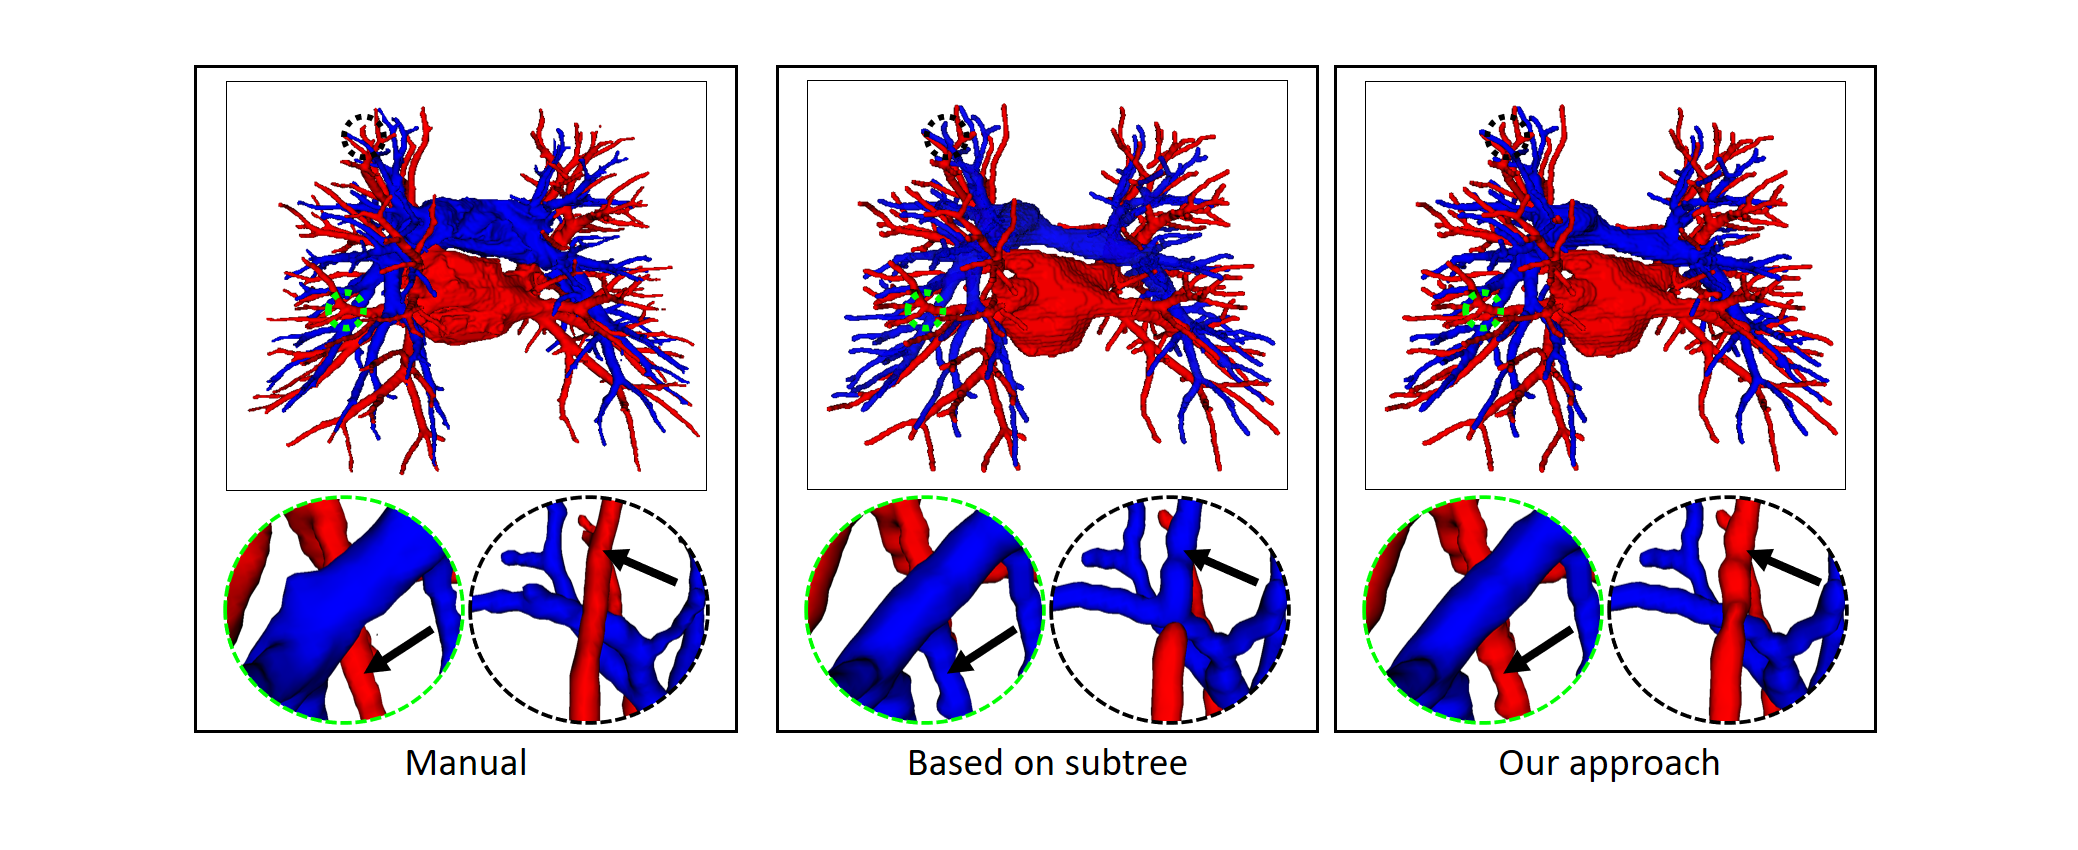

4.2.2 Topological postprocessing optimizer

To prove that the proposed topology optimizer is reasonable, we design different topology strategy optimizer to compare and analyze the experimental results. This approach includes the following: the precision of Twin-Pipe network (based on particle), the precision of topology branch refining (based on branch), the precision of topology subtree refining (based on subtree), and the refinement precision of the proposed topology optimizer. Table 3 shows an overview of the accuracy in all cases of the different topology strategy optimizers and reports on the sensitivity and specificity. The table 3 shows that our method is superior to branch-based and subtree-based topology optimizers, whose accuracies are 96.2%, 95.3%, and 93.2%, respectively.

Finally, the topology optimizer extracts the topology subtree and topology branch refinement results by the method in Section 2.3. The results of a topology subtree and topology branch are shown in Fig. 9. Then, we use topology subtrees and topology branches for postprocessing. As shown in Table 3, the proposed topology optimizer is superior to the subtree-based and branch-based topology optimization in accuracy. Fig. 14 and 15 show the reconstructed results of different topology strategy optimizers. The results in Fig. 14 show that when the number of points on the branch is small, and the branch-based topology optimization method is prone to predict errors. This finding is mainly because the branch-based refinement strategy focuses on the relationships within the branches and ignores the topological relationships between branches. As shown in Fig. 15, topology optimization based on subtree strategy is prone to prediction errors in the case of arterial-vein intersection. This finding is mainly because the arterial/venous intersection point in the extraction process of topological subtree is easily mistaken for the bifurcation point of arterial subtrees due to the complex structure of the vascular tree, arteries and veins interweave, and finally the venous branches are classified as arterial subtrees, resulting in the classification error.